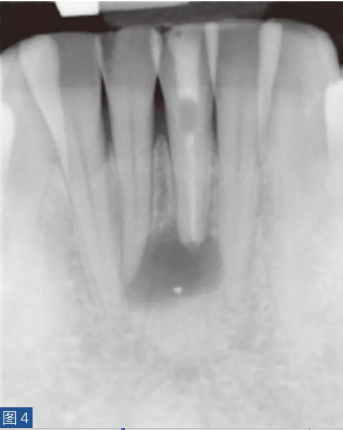

牙齒無(wú)癥狀的根尖周炎(圖4 和5)是由牙髓壞死引起的,并且通常是在癥狀性根尖周炎之后發(fā)生。因此,對(duì)冷、熱刺激和牙髓電活力測(cè)試無(wú)反應(yīng)。叩診無(wú)或者引起輕微的疼痛。如果骨皮質(zhì)已經(jīng)發(fā)生改變并且涉及到口腔軟組織,則觸診可引起輕微不適。放射學(xué)檢查,可能出現(xiàn)硬骨板不連續(xù)(破壞)以及根尖周和牙間組織的廣泛性破壞。

圖4:31 牙齒AAP。術(shù)前X線片?;颊咴V叩診和觸診時(shí)有輕微疼痛。